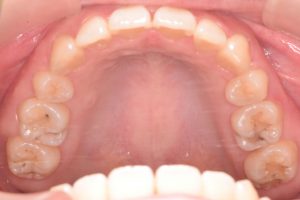

上あご

0000000011

0000000139